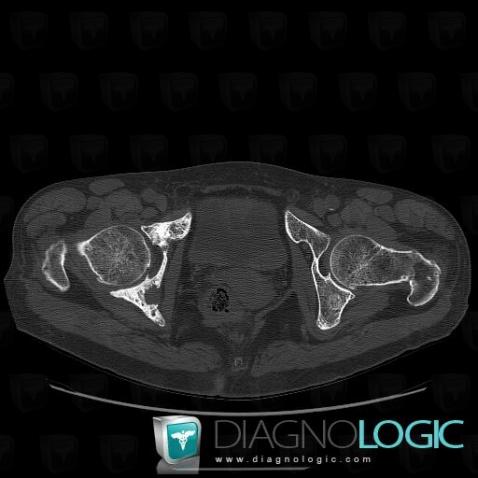

Metastasis, Ilium, CT

Here is the specific information in the key image above:

- Diagnosis Metastasis, Location(s) Ilium, with gamuts Well-defined osteolysis